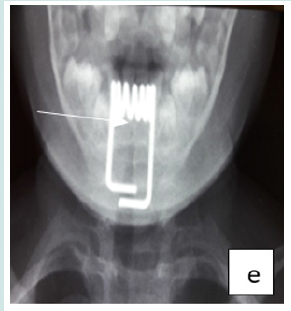

Cervico-thoracic X-ray performed in 211 cases (99%) showed opacity in 209 cases (99%). In one case, 2 circular opacities were observed, one of which had a double contour, indicating the ingestion of 2 foreign bodies (Figure 1: a, b, c, d, e, f). Foreign objects were a coin in 182 cases (85.4%), a shirt button in 4 cases (1.88%), a food in 7 cases (3.27%), and a flat battery in 3 cases (1.41%) (Table III). In 2 cases (1%) the EC was radiolucent.

Figure 6: f: circular esophageal CE of metallic tone, 2 opacities including one with a double contour (button batteries).